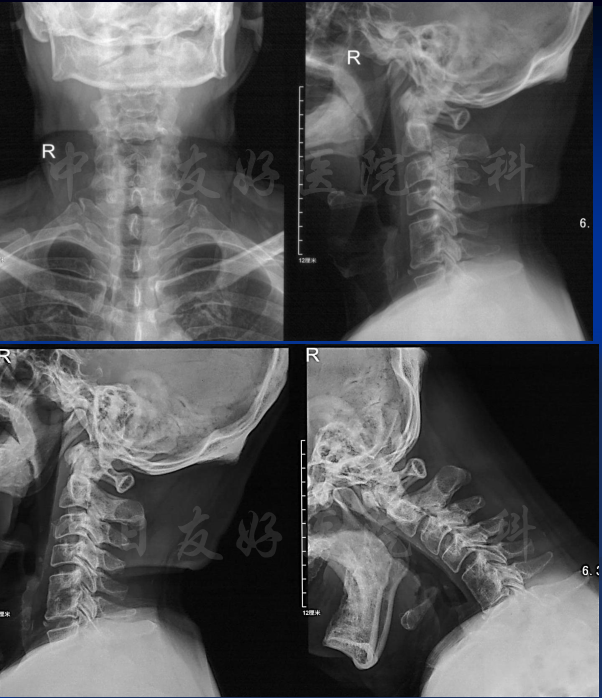

颈椎X片

颈椎MRI